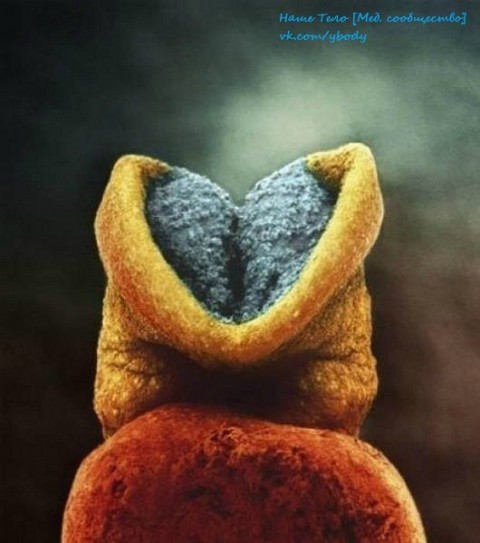

22 дня. Развитие эмбриона. Серым цветом — будущий головной мозг